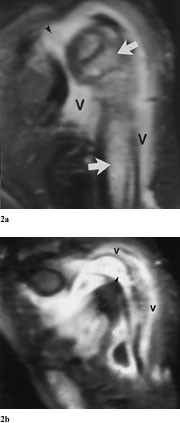

Pasient 1. En 14 måneder gammel gutt hadde smerter i venstre ankel og skulder, var ved innleggelsen afebril og i god allmenntilstand. Det var nedsatt aktiv bevegelse i ankel og skulder. Innkomstprøver viste CRP 58, leukocytter 16,2, hvorav 4,8 nøytrofile granulocytter. Røntgen av underarm indikerte fraktur gjennom proksimale del av humerusskaftet. Røntgen totalskjelett viste ikke andre frakturer. Skjelettscintigrafi seks dager etter avkreftet diagnosen akutt osteomyelitt, og han fikk derfor ingen behandling. To uker senere viste røntgen av venstre arm (fig 1) osteolytiske oppklaringer i proksimale, venstre humerus, oppfattet som mulig osteomyelitt eller tumor. Han var fortsatt afebril, men i noe redusert allmenntilstand, og venstre arm virket smertefull ved berøring. CRP var 40, leukocytter 12,9, hvorav 7,5 lymfocytter, og SR 104. Blodkultur og aspirat fra humerus gav ikke oppvekst av bakterier. Intravenøs antibiotikabehandling ble startet. MR av overarmen (fig 2) viste destruksjon i beinmarg med sentral nekrose i humerusmetafysen, oppfattet som sannsynlig osteomyelitt. Skjelettscintigrafi viste intet sikkert patologisk. Klinisk ble han gradvis bedre.

Røntgenkontroll etter 13 dagers behandling viste økende beintetthet i det aktuelle området uten tegn til nye osteolytiske områder. MR-kontroll etter tre ukers behandling viste klar bedring. Etter tre måneder hadde han full bevegelighet i skulderen.